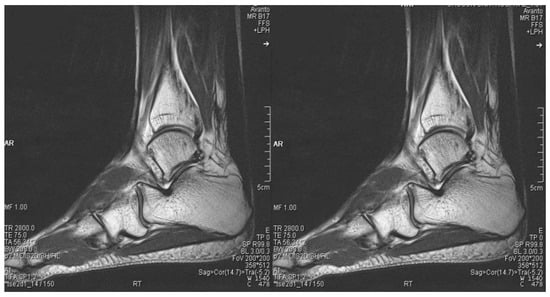

Figure 7. Postoperative (19 months after operation) sagittal magnetic resonance images of both ankles showing good continuity of the Achilles tendons.

2.3. Postoperative Care